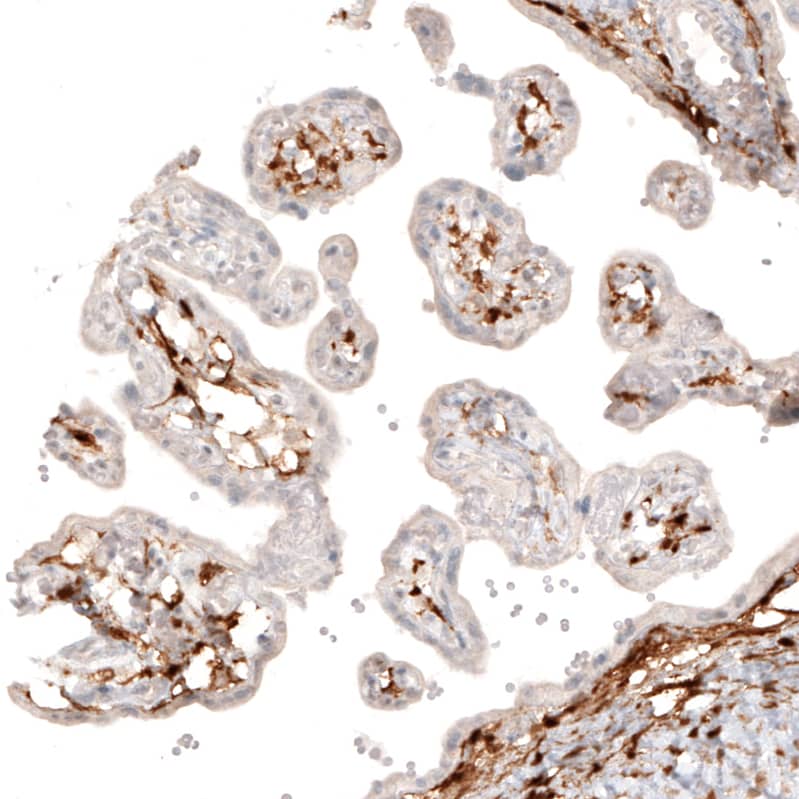

Staining of human placenta shows strong cytoplasmic positivity in a subset of cells in chorionic villi.